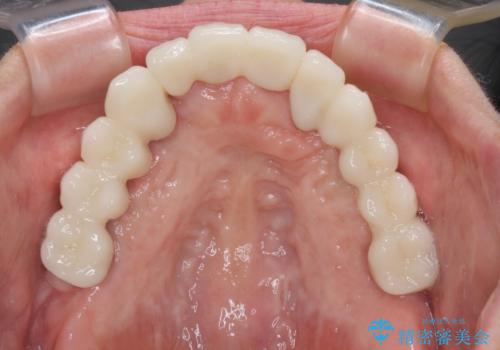

歯を抜かないといけない部分はインプラントとオールセラミッククラウンにより咬合を回復させ、歯周外科処置を行う歯については、同じくオールセラミッククラウンにて補綴治療を行うこととしました。

外科処置を多く行ったため、その待ち時間が長くかかり、さらには途中矯正治療も行なったので、治療期間は長期間となりました。

痛みには強い方であったため、治療はそれほど苦痛とは感じられず、毎回楽しく通院してくださいました。